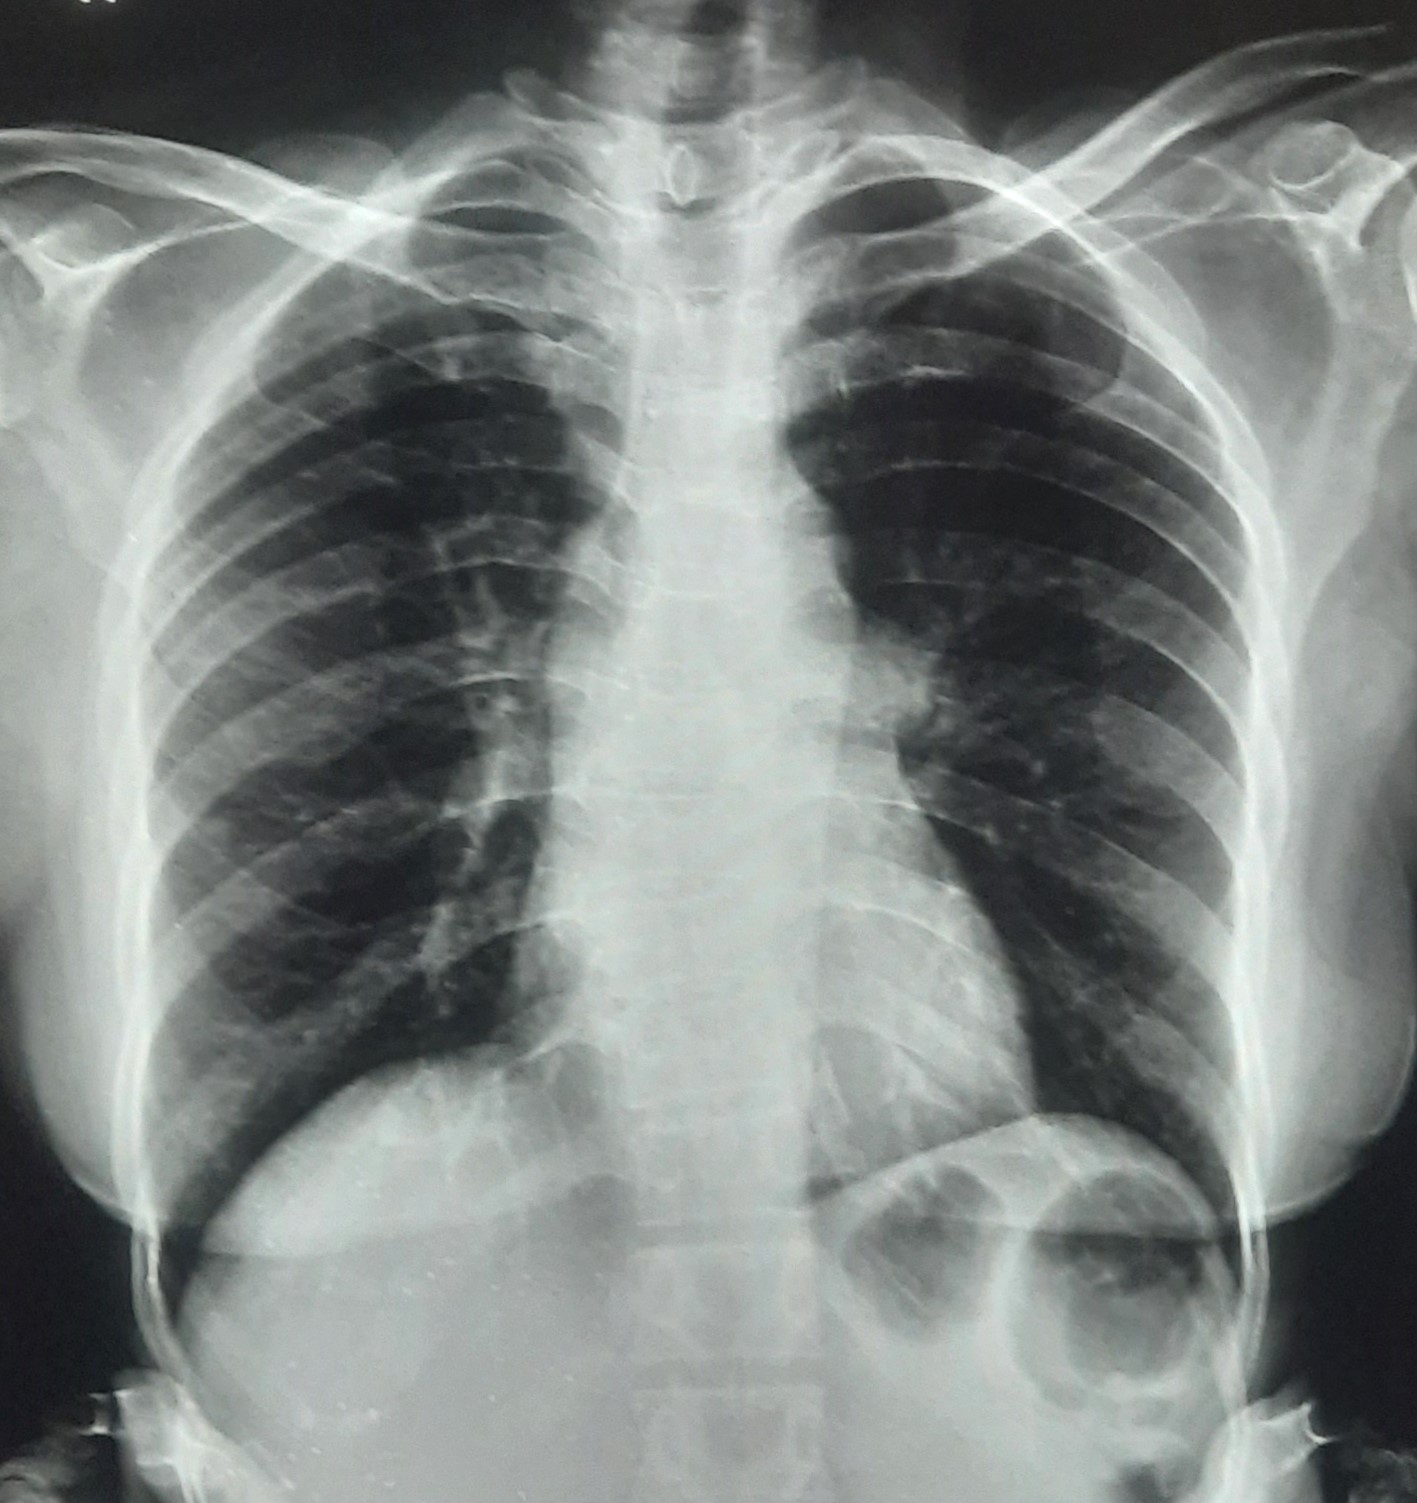

| 206 | IGGMC, Nagpur, Nagpur | P2 | 29-4266 | SHUBHAM URKUDE | Consent taken on Paper | 30 Yrs. |

Provisional Diag : PTB?

Final Diag : CLINICALLY DIAGNOSED PTB WITH OLD EPTB WITH LOSS TO FOLLOW UP IN CHRONIC ALCOHOLIC |

TB Case (Confirmed) | BILATERAL MIDDLE ZONE HAZZINESS/CONSOLIDATION | Abnormality visible on x-ray |